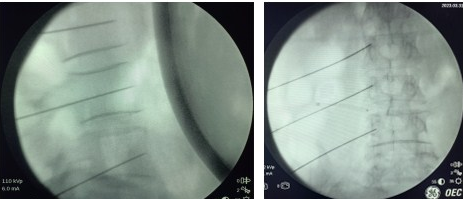

完善相关术前检查后,高建东主任为患者实施腰交感神经节射频消融治疗。术中用C型臂准确定位,手术在局麻下进行,且无切口。术后不久,患者的左下肢就出现了发热感,灼烧样疼痛得到缓解,小腿的木胀感消失了约80%。住院观察两天后,患者顺利出院。